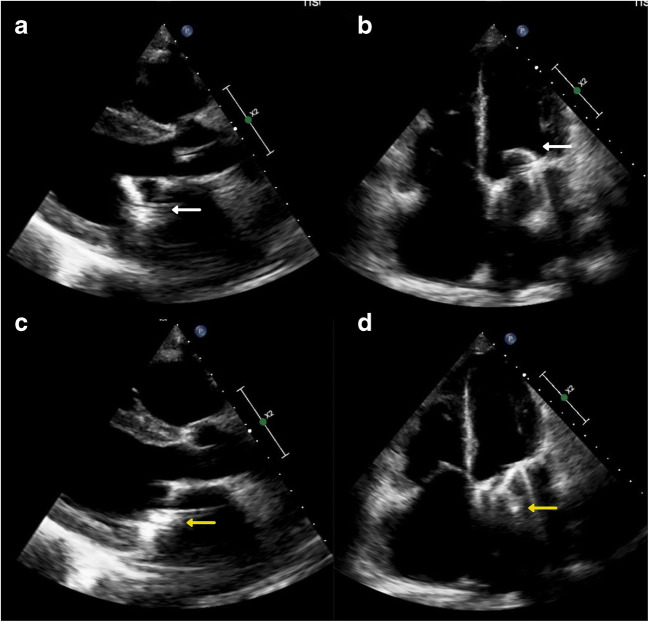

Fig. 1.

Parasternal long axis view (a) and apical 4 chamber view (b) showing complete opening of the disc with no restriction of movement (white arrow). Parasternal long axis view (c) and apical 4 chamber view (d) showing an unusual component of the mitral prosthesis protruding into the left atrium (yellow arrow)